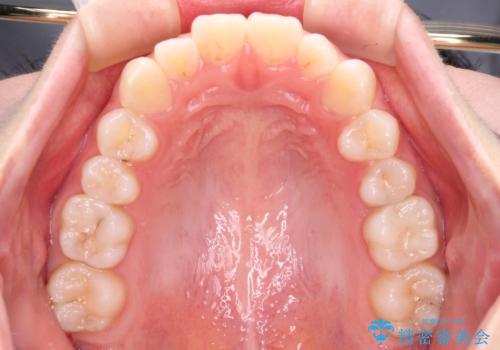

- 前歯の出っ歯と口元の閉じにくさを気にして来院された患者様です。

口元を積極的に引っ込めるために、上下左右の小臼歯4本を抜歯することとしました。

4本の歯を抜歯したことで、飛び出していた口元が引っ込み、横顔が大きく改善されました。